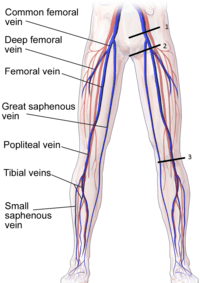

Sites of Compression for 3-Point Evaluation

- Common Femoral Vein

- Saphenofemoral Junction

- Popliteal Vein

- Common Femoral Vein and Saphenofemoral Junction

- Popliteal vein